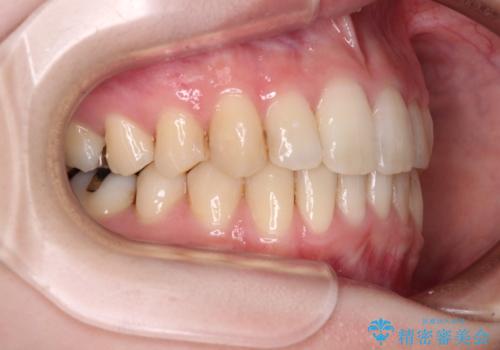

矯正治療後には、目立つ銀歯と隣接するむし歯をセラミックインレーにて修復治療することとしました。

左右ともに奥歯の咬み合わせには大きな問題がなく、窮屈な歯列を解決すれば歯列を整えることできたため、僅か1年で終えることができました。